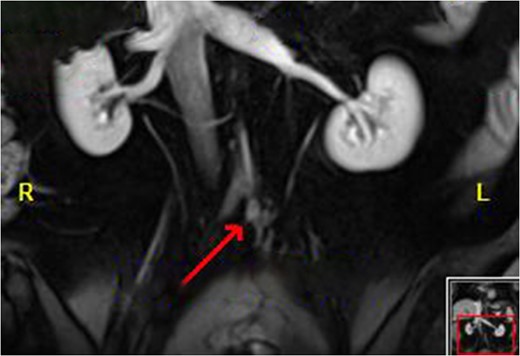

Colonoscopy revealed inflammatory polyps and an ulcerated circumferential mass 30 cm from the anal verge and positive for SCC. Positron emission tomography/computed tomography showed radiotracer uptake in the colon anastomosis, transverse colon, inferior mesenteric artery stump and mesenteric lymph nodes (Figure 1). A 2-cm liver segment VIII lesion was positive for SCC on core needle biopsy (Figure 2).

Disease of the inferior mesenteric artery stump. The arrow indicates the bulky disease.